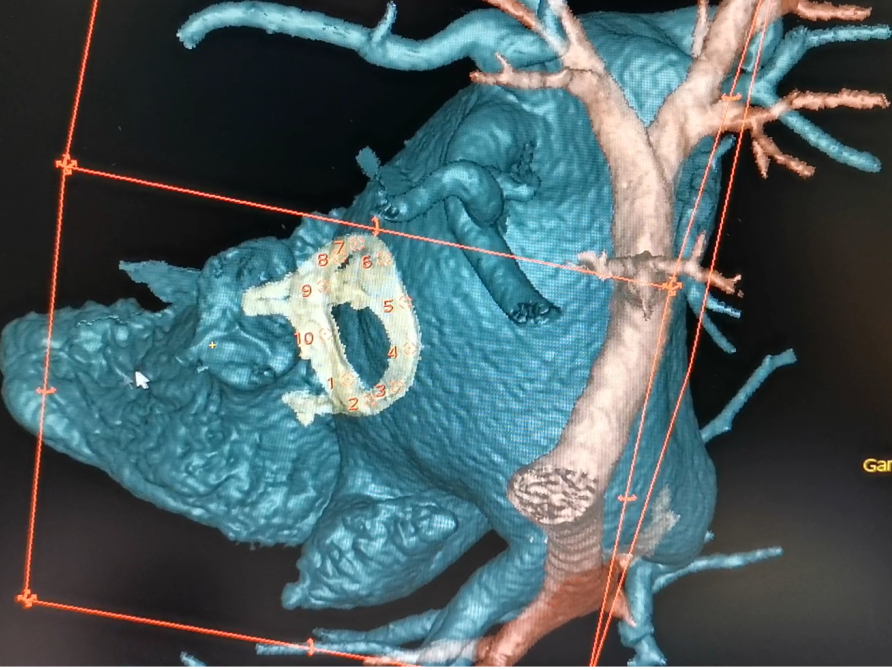

图1. 术前的3D打印和三维影像虚拟模拟技术

安贞医院心外科瓣膜中心(九病区)张海波教授团队率先国内开展介入瓣膜手术前的3D打印和三维影像虚拟模拟技术,对复杂结构病例进行术前充分多维度的分析,成功完成了多瓣膜生物瓣毁损的双瓣介入瓣中瓣、大动脉转位的生物瓣毁损介入手术、继往二尖瓣置换后的主动脉瓣重度狭窄、严重横位心二叶畸形、主动脉瓣四叶畸形、冠脉位置低至3.5mm等许多解剖结构复杂的介入瓣膜手术。再次基础上,近年来经过与公司研发团队多次筹备和反复尝试,在瓣膜中心李岩、王坚刚,麻醉卢家凯、武威,手术室许斌,影像科徐磊,超声张纯,体外循环黑飞龙、杨景,重症监护贾明等多学科协助下,成功在心脏主动脉瓣狭窄、主动脉瓣关闭不全、三尖瓣、二尖瓣生物瓣毁损等多种心脏瓣膜介入手术中利用手术虚拟影像融合技术,为国内首家全面完成手术虚拟融合介入瓣膜手术的中心,多项融合技术为国内首先完成。术中虚拟影像技术大大简化介入瓣膜手术流程,进一步提高了介入瓣膜手术精准度的把控,提高了手术安全性和成功率。